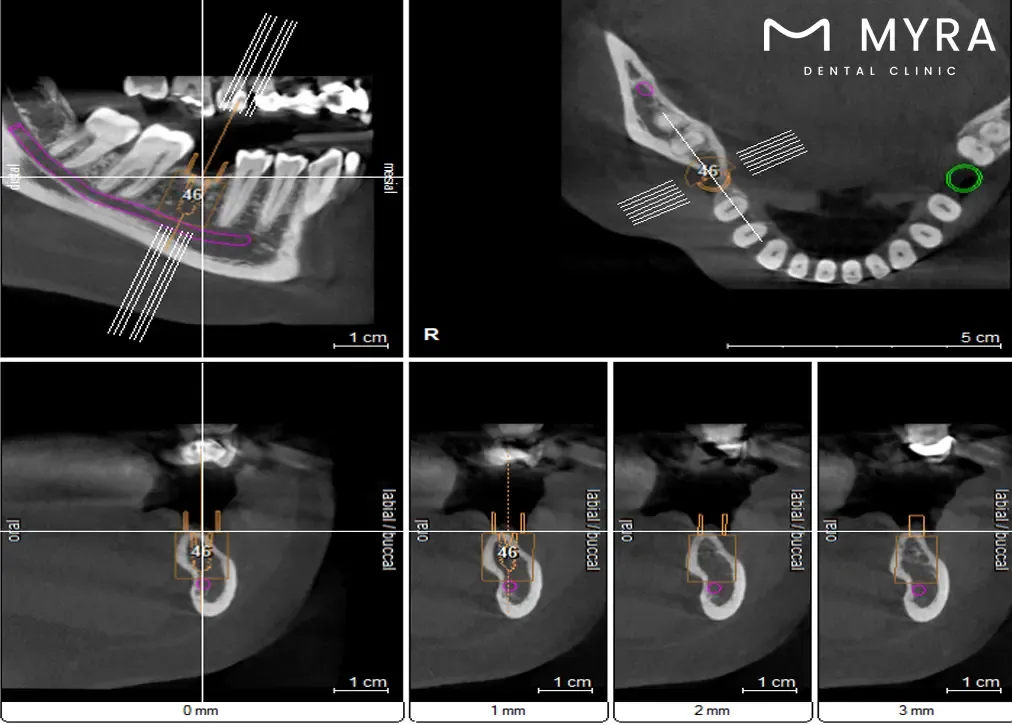

The dental filling treatment in Turkey has multiple steps, starting with the dentist’s comprehensive examination of the tooth. The initial phase includes X-rays to determine the level of decay. The tooth undergoes preparation afterward. The preparation includes numbing the area using anaesthetics, which require time to take effect.